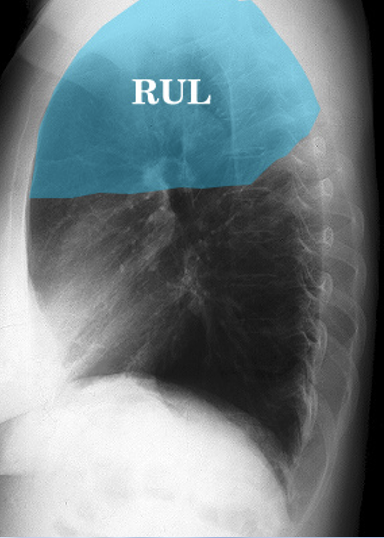

17

Q

What describes the anatomical position of the right upper lobe (RUL) ?

A

• Upper ⅓ of right lung

• Posteriorly, adjacent to first 3 - 5 ribs

• Anteriorly, reaches as far down as 4th rib